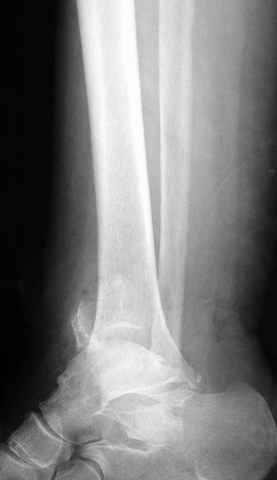

Pilon fracture:

-Появляется ориентир и остов, на чем можно строить восстановление, почему сперва малоберцовую, впервые обьяснили и описали (Pylon type and Ankle fractures) в середине 50х Rienau и Gay.

Восстановливая длину и ротацию малоберцовой кости, затем относительно легче произвести реставрацию остальных элементов перелома дистального эпиметафиза болшеберцовой кости.

где исследования на трупах показали, что малоберцовая кость участвует в стабильности голеностопного сустава, поддерживая наклон тарана (talar tilt) за счет связок. После ознакомления работой Ramsey в ортопедию ввели термин "при переломах голеностопного сустава смещенная

таранная кость следует за малоберцовой костью" т.е. связка не рвется, а тянет таран за собой, поэтому восстановление малоберцовой кости в

первую очередь, затем остальных элементов - стал классическим при лечении данной патолгии. Латеральная колонна (столб), дистальный

конец малоберцевой кости, к нему прикрепляется латеральный суставной фрагмент дистального эпиметафиза большеберцовой кости (как на снимке)

и таранная кость, которые при репозиции малоберцовой кости репонируются автоматически.